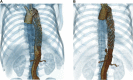

Persistent false lumen flow is common after thoracic endovascular aortic repair of type B aortic dissection and may contribute to continued aortic aneurysmal degeneration. We report an innovative technique of intercostal artery embolization within the false lumen for a patient who had incomplete false lumen thrombosis and progressive aortic enlargement after thoracic endovascular aortic repair of chronic type B aortic dissection. Technical success was facilitated by use of on-table cone beam computed tomography angiography, virtual vessel marking, and modern endovascular tools. The patient had no complications from the procedure. Postoperative imaging demonstrated complete thoracic false lumen thrombosis and favorable aortic remodeling with reduction in maximal aortic diameter.